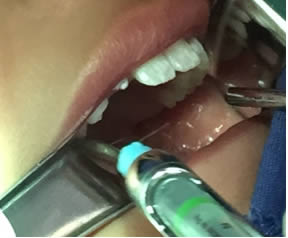

• Se colocó anestesia tópica y se infiltró localmente (lidocaína con epinefrina de 1: 100 000 al 2 %) a cada lado del frenillo lingual bloqueando nervio lingual bilateralmente. (Figuras 1 y 2).

Figura 1. Anestesia Local a cada lado del frenillo.

Figura 2. Anestesia Local del nervio lingual bilateralmente